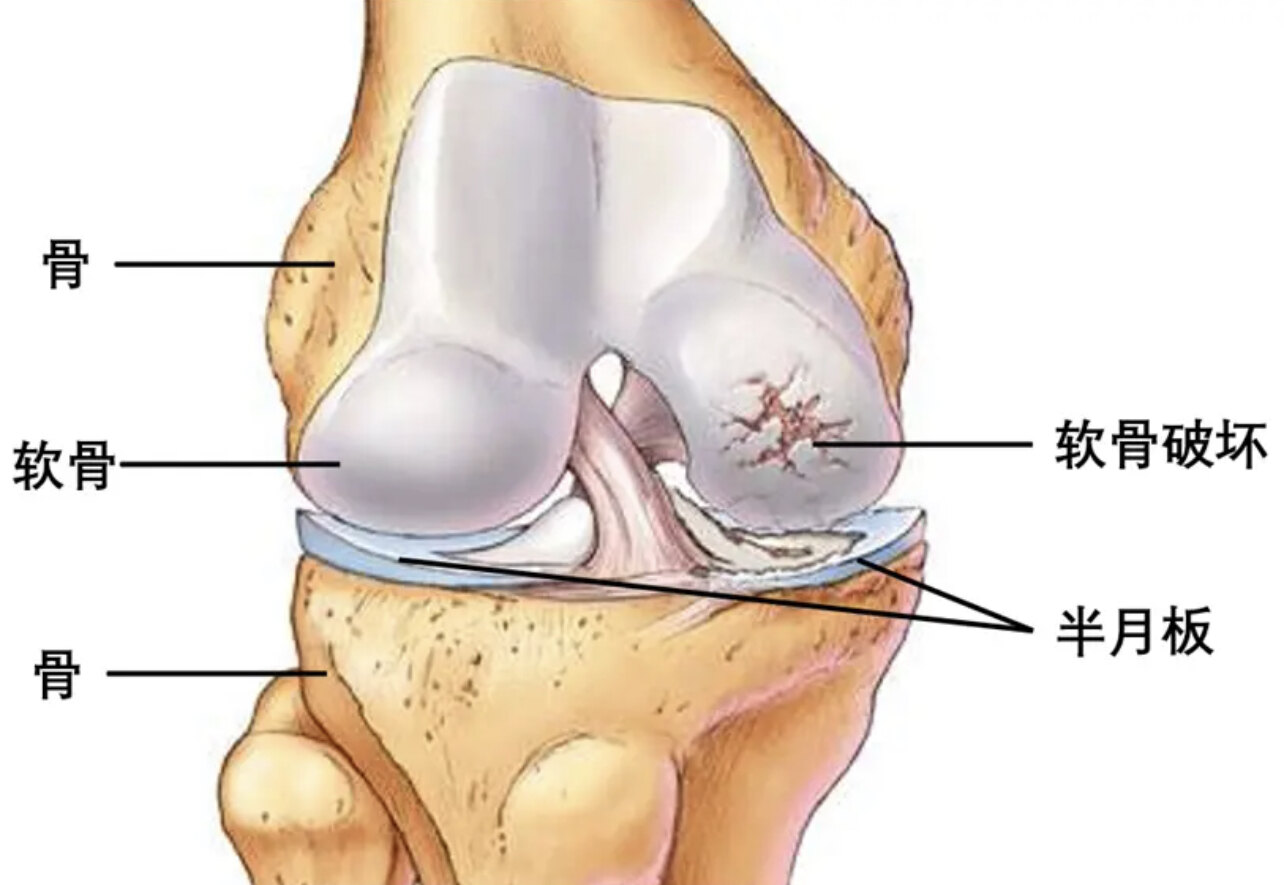

骨性關(guān)節(jié)炎概述骨性關(guān)節(jié)炎,又稱為退行性關(guān)節(jié)病,是一種最常見的關(guān)節(jié)炎類型。它主要由關(guān)節(jié)軟骨的磨損和退化引起,這種磨損會逐漸影響整個關(guān)節(jié)結(jié)構(gòu),包括鄰近的骨頭、關(guān)節(jié)液和周圍的肌肉。成因骨性關(guān)節(jié)炎可能由多種因素引起,包括:1.年齡:隨著年齡增長,關(guān)節(jié)軟骨的自然磨損增加。2.肥胖:過重的體重增加了對關(guān)節(jié)的負擔。3.關(guān)節(jié)受傷:歷史上的關(guān)節(jié)損傷可以增加關(guān)節(jié)炎的風險。4.遺傳因素:家族歷史可能影響個體發(fā)展骨性關(guān)節(jié)炎的風險。癥狀骨性關(guān)節(jié)炎的常見癥狀包括:1.關(guān)節(jié)疼痛:活動后加劇。2.僵硬:特別是早上起床或長時間不活動后。3.腫脹:由于炎癥和積液。4.活動范圍受限:關(guān)節(jié)的靈活性下降。5.關(guān)節(jié)變形:在一些嚴重的案例中。診斷1.病史和體格檢查:醫(yī)生會評估癥狀和進行關(guān)節(jié)檢查。2.影像學檢查:X光或MRI可用于評估關(guān)節(jié)的損傷程度。治療骨性關(guān)節(jié)炎的治療目標是減輕癥狀和改善生活質(zhì)量:1.生活方式改變:減重、適度運動和保持活動。2.物理治療:加強肌肉,提高關(guān)節(jié)穩(wěn)定性。3.藥物治療:包括止痛藥和非甾體抗炎藥。4.手術(shù)治療:在嚴重案例中,可能需要關(guān)節(jié)置換手術(shù)。預(yù)防1.保持健康體重:減少關(guān)節(jié)的負擔。2.規(guī)律運動:增強關(guān)節(jié)周圍的肌肉,提高靈活性。3.避免關(guān)節(jié)損傷:采取預(yù)防措施減少運動傷害。結(jié)語雖然骨性關(guān)節(jié)炎是一種慢性疾病,但通過適當?shù)墓芾砗椭委?,許多人仍能保持活躍的生活方式。如果您認為自己可能患有骨性關(guān)節(jié)炎,請咨詢醫(yī)生以獲取正確的診斷和治療建議。

膝關(guān)節(jié)長骨刺、軟骨損壞、關(guān)節(jié)變形,疼痛腫脹無力,致畸致殘是骨關(guān)節(jié)炎(OA)的可怕之處。再生治療旨在修復(fù)和替換受損的細胞和組織。再生治療里的干細胞治療方法已經(jīng)說了好多年了,但是在國內(nèi)始終沒有普及開來,那么目前干細胞治療膝關(guān)節(jié)OA的研究進展究竟如何?技術(shù)到底成不成熟?效果到底好不好?安全性如何?實際上全世界已經(jīng)做了不少研究了,本文萬醫(yī)生帶各位了解一下。骨關(guān)節(jié)炎(OA)是一種常見的慢性疾病,是老年人主要的身體疼痛和殘疾原因。目前已經(jīng)成為世界上第四大殘疾原因。OA通常影響膝蓋、髖部、手部、腳部和脊柱。膝蓋是最常受影響的部位,膝關(guān)節(jié)骨關(guān)節(jié)炎(KOA)占全球OA負擔的近85%,OA的典型癥候群包括慢性疼痛、僵硬、活動受限和關(guān)節(jié)壓痛。女性性別、年齡、肥胖、遺傳因素和氧化應(yīng)激等多種風險因素增加了發(fā)展OA的機會。由于老齡化、肥胖以及受損關(guān)節(jié)數(shù)量的增加等綜合因素,OA在當今變得更加普遍,預(yù)計有2.5億人受到該病之苦。OA的特點是細胞外基質(zhì)的退化導(dǎo)致關(guān)節(jié)軟骨的喪失,炎癥在軟骨破壞中發(fā)揮著重要作用。對于膝關(guān)節(jié)骨關(guān)節(jié)炎的治療,文獻中報告了50多種藥物、非藥物和手術(shù)治療方法。然而,目前治療膝關(guān)節(jié)骨關(guān)節(jié)炎的最主流的,除了關(guān)節(jié)置換外,大部分治療方法通常通過控制炎癥,減緩關(guān)節(jié)軟骨的破壞。目的在于減少疼痛,維持或改善關(guān)節(jié)功能,避免發(fā)生殘疾和失能,而不是重生關(guān)節(jié)軟骨。為了重生關(guān)節(jié)軟骨,人們進行了各種努力,包括細胞治療和組織工程。自體軟骨細胞移植是研究最廣泛的方法之一,目前臨床結(jié)果比較正面。然而,自體軟骨細胞移植具有固有的缺點,例如技術(shù)本身可能導(dǎo)致進一步軟骨損傷和退化。該手術(shù)需要分為兩階段進行,即取材、培養(yǎng)和再植入。培養(yǎng)期間軟骨細胞去分化可能導(dǎo)致變?yōu)槔w維軟骨而非透明軟骨。自體軟骨細胞移植只局限用于局部軟骨缺損,對骨關(guān)節(jié)炎中出現(xiàn)的廣泛軟骨缺損無可奈何,這表明有必要尋找骨關(guān)節(jié)炎中軟骨再生的不同方法。間充質(zhì)干細胞(MSCs)也一直是軟骨再生的新興方案。與自體軟骨細胞移植不同,MSCs用于人體關(guān)節(jié)軟骨再生仍處于研究階段。最近,一些學者報告了將MSCs直接注射到膝關(guān)節(jié)用于治療骨關(guān)節(jié)炎中的局部缺陷或更廣泛的軟骨缺損的臨床結(jié)果。如果直接將MSCs注射到關(guān)節(jié)腔中可以轉(zhuǎn)化為臨床實踐,將帶來很大的優(yōu)勢,因為它將避免手術(shù)及相關(guān)的副作用,例如軟骨肥大和骨化、異種移植物引起的免疫反應(yīng)和疾病傳播。更重要的是,注射的簡便性和便利性可以為老年患者提供更好的治療機會,特別是對于伴有各種內(nèi)科疾病、不適合做手術(shù)的患者。作為廣泛分布在骨髓、骨膜、骨松質(zhì)、脂肪墊組織、滑膜和其他一些組織中的多能細胞,間充質(zhì)干細胞(MSCs)在促進軟骨細胞再生和分化為軟骨方面具有巨大潛力。MSCs最初是從骨髓中分離出來的,后來也從其他組織中分離出來,如脂肪組織、胎盤、臍帶、臍帶血、牙髓和羊膜液。MSCs具有自我更新和分化為軟骨的能力,并具有抑制炎癥和免疫調(diào)節(jié)能力。許多臨床前和臨床研究證實了MSCs作為OA治療的一種新型治療策略的潛力。目前主要的MSCs分為以下三類:1骨髓來源的MSCs(BM-MSCs)、2脂肪組織來源的MSCs(AD-MSCs)3臍帶來源的MSCs(UC-MSCs)。不同來源的MSCs具有不同的特征,各自有其優(yōu)點和缺點。就組織中MSCs的含量而言,臍帶(UC-MSCs)最高,其次是脂肪(AD-MSCs)。就MSCs增殖能力而言,臍帶來源的MSCs具有明顯優(yōu)勢,其次是脂肪(AD-MSCs)和骨髓(BM-MSCs)。在免疫調(diào)節(jié)能力方面,臍帶(UC-MSCs)、脂肪來源的MSCs(AD-MSCs)對比骨髓MSCs具有更強的免疫調(diào)節(jié)能力。此外,臍帶MSCs分泌的細胞生長因子多于骨髓MSCs。不同來源干細胞的優(yōu)缺點總結(jié)在下表中。MSCs具有促進軟骨形成、血管化、抗炎和免疫調(diào)節(jié)的能力,是作為細胞再生療法的理想特性。目前已經(jīng)有大量體外和動物模型研究證實了MSCs促進軟骨再生的潛力。近年來,研究并不僅限于動物模型。一些臨床試驗已經(jīng)證明了來自骨髓、脂肪組織和臍帶血的MSCs在治療骨關(guān)節(jié)炎方面具有潛在的療效。由于其簡單易得性、快速的細胞增殖、長期維持分化能力和減少免疫排斥的特點,骨髓來源的MSCs是治療性MSCs最廣泛使用的來源。20多年前,Wakitani等進行了第一項關(guān)于應(yīng)用BM-MSCs移植治療關(guān)節(jié)軟骨缺損的臨床研究。該試驗招募了24名患有膝關(guān)節(jié)骨關(guān)節(jié)炎的患者,他們接受了高脛骨截骨手術(shù),其中一半接受了自體BM-MSC移植,另一半為對照組。移植后42周,樣本組織的幾乎所有區(qū)域均觀察到異染色,部分觀察到透明軟骨樣組織。關(guān)節(jié)鏡和組織學分級評分在細胞移植組中優(yōu)于無細胞對照組,表明BM-MSC移植對治療骨關(guān)節(jié)炎是合適的。Wong等進行的一項為期2年的自體BM-MSC移植臨床試驗納入了56名接受高脛骨截骨和微裂的單膝骨關(guān)節(jié)炎患者。細胞接受組的Tegner、Lysholm、IKDC和MOCART評分更好,表明自體BM-MSC移植對骨關(guān)節(jié)炎治療是有效的。Vangsness等進行的試驗中,納入了55名接受了部分內(nèi)側(cè)半月板切除的患者,分別在治療組接受兩個不同劑量的同種異體BM-MSCs。經(jīng)過2年的隨訪,未發(fā)現(xiàn)臨床不良反應(yīng),細胞接受組的半月板體積增加,根據(jù)視覺模擬評分(VAS)評估,疼痛顯著減輕。Lamo-Espinosa等進行的一項多中心隨機的I/II期臨床試驗證明了兩個不同劑量的BM-MSC移植與透明質(zhì)酸(HA)相比在30名膝關(guān)節(jié)骨關(guān)節(jié)炎患者中的長期效果。經(jīng)過4年的隨訪,細胞接受組,尤其是高劑量組,VAS和WOMAC評分更好,表明BM-MSCs在長期的臨床和功能改善中具有治療潛力。Davatchi等進行的一項為期5年的自體BM-MSC移植的長期試驗在4名中度至重度膝關(guān)節(jié)骨關(guān)節(jié)炎患者中顯示了類似的結(jié)果。治療后6個月,步行時間、上樓梯表現(xiàn)、腫脹疼痛、髕骨摩擦感、屈曲攣縮和VAS等所有參數(shù)均得到改善,5年后雖有下降,但仍然優(yōu)于基線水平。由于其比BM-MSCs更大的增殖和分化潛力,脂肪來源的MSCs是治療性MSCs的另一個具有吸引力的細胞來源。近年來的幾項臨床試驗已經(jīng)證明了AD-MSCs在治療中的有效性。Pers等在一項I期劑量遞增試驗中,18名癥狀明顯且病情嚴重的膝關(guān)節(jié)骨關(guān)節(jié)炎患者接受了自體AD-MSCs的三個劑量:低劑量(2×106細胞)、中劑量(10×106細胞)和高劑量(50×106細胞)。六個月的隨訪顯示沒有臨床不良反應(yīng),接受低劑量AD-MSCs治療的患者經(jīng)歷了明顯的疼痛緩解和功能改善。這項研究表明了AD-MSCs在膝關(guān)節(jié)骨關(guān)節(jié)炎治療中的安全性、耐受性和初步有效性;然而,需要進行更大規(guī)模、更嚴格的長期試驗以進一步評估其效果。Koh等進行的臨床試驗旨在評估18至50歲之間的80名中度至重度膝關(guān)節(jié)骨關(guān)節(jié)炎患者中AD-MSCs聯(lián)合微裂和單純微裂治療的療效。經(jīng)過24個月的隨訪,接受AD-MSCs治療的組顯示出更好的組織修復(fù)信號強度和KOOS疼痛和癥狀亞分數(shù),但在其他亞分數(shù)(如日常生活活動、運動和娛樂以及生活質(zhì)量)方面沒有顯著差異,表明AD-MSCs在組織修復(fù)和緩解疼痛方面具有潛力Lee等近年來進行了一項IIb期隨機、安慰劑對照的AD-MSCs治療膝關(guān)節(jié)骨關(guān)節(jié)炎的臨床試驗,納入了24名患者。六個月的隨訪結(jié)果顯示,接受AD-MSCs治療的組具有更好的安全性、增加的WOMAC評分、功能改善和疼痛減輕,表明AD-MSCs在治療中的潛力。Chris等對OA患者進行關(guān)節(jié)腔內(nèi)注射BM-MSCs的臨床試驗中,使用關(guān)節(jié)鏡檢和磁共振的方法證實了在光禿禿的只剩骨頭的關(guān)節(jié)表面出現(xiàn)了軟骨再生。自體脂肪組織源MSCs(ADMSCs)注射前后6個月的關(guān)節(jié)鏡檢查顯示了與臨床和放射學結(jié)果一致的發(fā)現(xiàn)。在肉眼下,再生軟骨在內(nèi)側(cè)股骨和脛骨髁的ICRS3級最嚴重退變區(qū)域形成,而在外側(cè)區(qū)和髕骨的退變較輕的區(qū)域幾乎看不到。再生軟骨呈光澤的白色,表面光滑。用探針觸摸時,在內(nèi)側(cè)股骨髁上感覺堅固,就像健康的關(guān)節(jié)軟骨一樣,而在內(nèi)側(cè)脛骨髁上感覺較不堅固。未發(fā)現(xiàn)游離體、肥大或異常鈣化。用已校準的探針測量的軟骨缺損大小顯示:在高劑量組中,內(nèi)側(cè)股骨髁的軟骨缺損從1,225.7±282.8mm2減少到837.8±278.9mm2(減少32%;p=.003),而內(nèi)側(cè)脛骨髁的軟骨缺損從352.3±77.6mm2減少到126.3±43.8mm2(減少64%;p=.008)。總的來說,將1.0×108個自體脂肪組織源MSCs(ADMSCs)注射到骨關(guān)節(jié)炎膝關(guān)節(jié)中,能夠改善膝關(guān)節(jié)的功能和疼痛,且沒有引起不良事件。影像學、關(guān)節(jié)鏡和組織學測量一致顯示,通過透明樣關(guān)節(jié)軟骨的再生,關(guān)節(jié)軟骨缺損面積顯著減少。UC-MSCs相對于BM-MSCs具有更高的增殖能力、活躍的分化能力和卓越的免疫調(diào)節(jié)能力,UC-MSCs是一種新的干細胞療法的來源。Wang等對36名中度或重度膝關(guān)節(jié)骨關(guān)節(jié)炎患者進行了為期6個月的UC-MSC移植的安全性和有效性研究。結(jié)果顯示,與對照組相比,細胞治療組的Lysholm、WOMAC和SF-36評分更好。在注射后,細胞治療組在疼痛和腫脹方面表現(xiàn)出更高的發(fā)生率,但在隨訪期間未發(fā)現(xiàn)膝關(guān)節(jié)疼痛的復(fù)發(fā),表明UC-MSCs在關(guān)節(jié)改善中具有治療潛力。Liu等進行的一項臨床試驗也獲得了類似的結(jié)果,其中3名膝關(guān)節(jié)骨關(guān)節(jié)炎患者通過關(guān)節(jié)內(nèi)注射接受了5-7×107UC-MSCs。經(jīng)過3個月的隨訪,這3名患者表現(xiàn)出疼痛緩解和日常活動能力恢復(fù)。最近,Pak在膝關(guān)節(jié)骨關(guān)節(jié)炎患者中進行了一個臍帶血來源的間充質(zhì)干細胞(UCB-MSC)應(yīng)用的臨床試驗,患者患有全層軟骨缺陷。對接受UCB-MSC治療的64名患者進行的術(shù)后1年的二次關(guān)節(jié)鏡手術(shù)回顧顯示,與基線相比,IKDC、WOMAC、VAS和OAS評分均有所改善,表明UCB-MSCs在緩解疼痛和改善功能方面具有治療選擇的潛力。Jose等應(yīng)用UCB-MSC治療膝關(guān)節(jié)骨關(guān)節(jié)炎,設(shè)計了和玻璃酸鈉進行對照的隨機臨床試驗中證實,多次MSCs注射優(yōu)于單次MSC注射和單純玻璃酸鈉注射。到目前為止,已有多項臨床試驗證明了BM-MSCs、AD-MSCs和UC-MSCs在治療骨關(guān)節(jié)炎中的安全性和潛在療效。然而,我們必須承認,一些試驗的樣本量有限,缺乏嚴格的對照和相對較短的隨訪時間。需要進行更大規(guī)模、更嚴格的對照、更謹慎的處理和長期隨訪的臨床試驗以進行進一步的評估。1.WakitaniS,ImotoK,YamamotoT,SaitoM,MurataN,YonedaM.Humanautologouscultureexpandedbonemarrowmesenchymalcelltransplantationforrepairofcartilagedefectsinosteoarthriticknees.OsteoarthritisCartilage.2002;10:199–206.2.WongKL,LeeKB,TaiBC,LawP,LeeEH,HuiJH.Injectableculturedbonemarrow-derivedmesenchymalstemcellsinvaruskneeswithcartilagedefectsundergoinghightibialosteotomy:aprospective,randomizedcontrolledclinicaltrialwith2years’follow-up.Arthroscopy.2013;29:2020–2028.3.VangsnessCTJr,FarrJ2nd,BoydJ,DellaeroDT,MillsCR,LeRoux-WilliamsM.Adulthumanmesenchymalstemcellsdeliveredviaintra-articularinjectiontothekneefollowingpartialmedialmeniscectomy:arandomized,double-blind,controlledstudy.JBoneJointSurgAm.2014;96:90–98.4.Lamo-EspinosaJM,MoraG,BlancoJF,Granero-MoltoF,Nunez-CordobaJM,Sanchez-EcheniqueC,BondiaJM,AquerretaJD,AndreuEJ,OrnillaE,VillaronEM,Valenti-AzcarateA,Sanchez-GuijoF,DelCanizoMC,Valenti-NinJR,ProsperF.Intra-articularinjectionoftwodifferentdosesofautologousbonemarrowmesenchymalstemcellsversushyaluronicacidinthetreatmentofkneeosteoarthritis:multicenterrandomizedcontrolledclinicaltrial(phaseI/II)JTranslMed.2016;14:246–255.5.PersYM,RackwitzL,FerreiraR,PulligO,DelfourC,BarryF,SensebeL,CasteillaL,FleuryS,BourinP,NoelD,CanovasF,CytevalC,LisignoliG,SchrauthJ,HaddadD,DomergueS,NoethU,JorgensenC.Adiposemesenchymalstromalcell-basedtherapyforsevereosteoarthritisoftheknee:aphaseidose-escalationtrial.StemCellsTranslMed.2016;5:847–856.6.KohYG,KwonOR,KimYS,ChoiYJ,TakDH.Adipose-derivedmesenchymalstemcellswithmicrofractureversusmicrofracturealone:2-yearfollow-upofaprospectiverandomizedtrial.Arthroscopy.2016;32:97–109.7.LeeWS,KimHJ,KimKI,KimGB,JinW.Intra-articularinjectionofautologousadiposetissue-derivedmesenchymalstemcellsforthetreatmentofkneeosteoarthritis:aphaseiib,randomized,placebo-controlledclinicaltrial.StemCellsTranslMed.2019;8:504–511.8.WangY,JinW,LiuH,CuiY,MaoQ,FeiZ,XiangC.Curativeeffectofhumanumbilicalcordmesenchymalstemcellsbyintra-articularinjectionfordegenerativekneeosteoarthritis.ZhongguoXiuFuChongJianWaiKeZaZhi.2016;30:1472–1477.9.LiuC,YangY,HeG.Efficacyandsafetyofumbilicalcord-mesenchymalstemcellstransplantationfortreatingosteoarthritis.OsteoarthrCartilage.2017;25:S389–S389.10.PakJY.Clinicaloutcomesofhumanumbilicalcordbloodderivedmesenchymalstemcellsapplicationinkneeosteoarthritispatients.OsteoarthrCartilage.2019;27:S511–S511.11.DavatchiF,SadeghiAbdollahiB,MohyeddinM,NikbinB.Mesenchymalstemcelltherapyforkneeosteoarthritis:5yearsfollow-upofthreepatients.IntJRheumDis.2016;19:219–225.12.JoseMatas,MarioOrrego,DiegoAmenabar,CatalinaInfante,RafaelTapia-Limonchi,MariaIgnaciaCadiz,FranciscaAlcayaga-Miranda,PazL.González,EmilioMuse,MarounKhoury,FernandoE.Figueroa,FranciscoEspinoza,UmbilicalCord-DerivedMesenchymalStromalCells(MSCs)forKneeOsteoarthritis:RepeatedMSCDosingIsSuperiortoaSingleMSCDoseandtoHyaluronicAcidinaControlledRandomizedPhaseI/IITrial,StemCellsTranslationalMedicine,Volume8,Issue3,March2019,Pages215–22413.ChrisHyunchulJo,YoungGilLee,WonHyoungShin,HyangKim,JeeWonChai,EuiCheolJeong,JiEunKim,HackjoonShim,JiSunShin,IlSeobShin,JeongChanRa,SoheeOh,KangSupYoon,Intra‐ArticularInjectionofMesenchymalStemCellsfortheTreatmentofOsteoarthritisoftheKnee:AProof‐of‐ConceptClinicalTrial,StemCells,Volume32,Issue5,May2014,Pages1254–1266,14.ZhuC,WuW,QuX.Mesenchymalstemcellsinosteoarthritistherapy:areview.AmJTranslRes.2021Feb15;13(2):448-461.PMID:33594303;PMCID:PMC7868850.